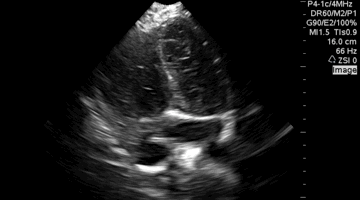

QA of the day. Nice PSS! Global hypokinesis, low EF. Mitral valve view, septum and moderator band. #pocus # foamed # foamus # meded